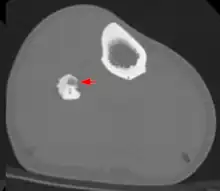

Radiographs in osteoid osteoma typically show a round lucency, containing a dense sclerotic central nidus (the characteristic lesion in this kind of tumor) surrounded by sclerotic bone. The nidus is seldom larger than 1.5 cm.

The lesion can in most cases be detected on CT scan, bone scans and angiograms. Plain radiographs are not always diagnostic. MRI adds little to the CT findings which are useful for localisation. Radionuclide scanning shows intense uptake which is useful for localisation at surgery using a hand held detector, and for confirmation that the entire lesion has been removed.[8][9]

Recently, CT guided radiofrequency ablation has emerged as a less invasive alternative to surgical resection. In this technique, which can be performed under conscious sedation, an RF probe is introduced into the tumor nidus through a cannulated needle under CT guidance and heat is applied locally to destroy tumor cells. Since the procedure was first introduced for the treatment of osteoid osteomas in the early 1990s,[12] it has been shown in numerous studies to be less invasive and expensive, to result in less bone destruction and to have equivalent safety and efficacy to surgical techniques, with 66 to 96% of patients reporting freedom from symptoms.[13][14][15] While initial success rates with RFA are high, symptom recurrence after RFA treatment has been reported, with some studies demonstrating a recurrence rate similar to that of surgical treatment.[16]